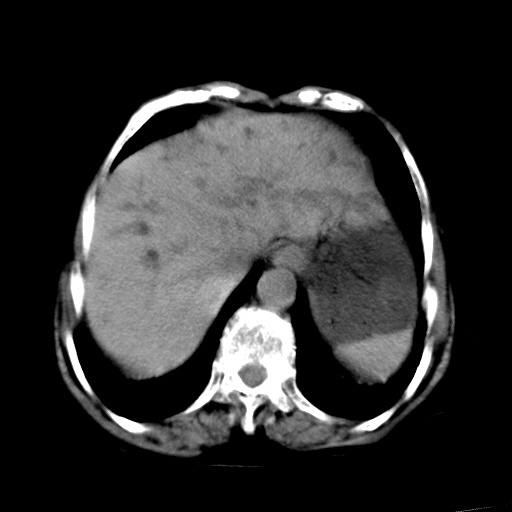

以下是引用杀毒软件在2009-3-4 17:38:00的发言:[br]为何没有喝照影剂呀? 胆总管及肝内胆管扩张,增强吧。[br][br]考虑-----十二指肠占位----建议----十二指肠镜检查[br][br]

以下是引用jiangjing在2009-3-4 17:45:00的发言:[br]低位胆道梗阻。十二指肠降段局部管壁增厚。扫描效果不理想,建议ct增强及ercp。

以下是引用杀毒软件在2009-3-4 17:38:00的发言:[br]为何没有喝照影剂呀? 胆总管及肝内胆管扩张,。增强吧。[br][br]考虑-----十二指肠占位----建议----十二指肠镜检查[br][br][br][br][本贴已被 杀毒软件 于 2009-3-4 17:56:38 修改过]